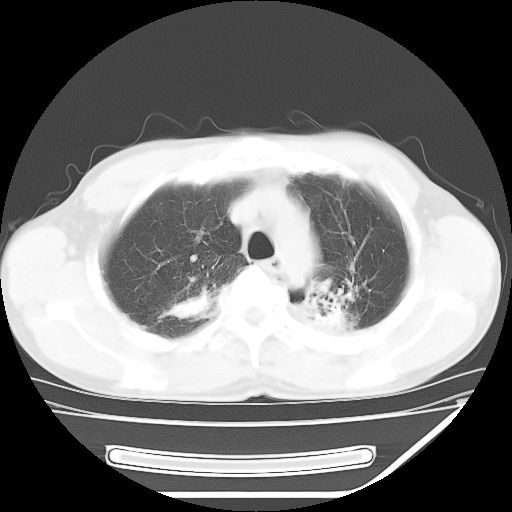

男,59岁,“结核性胸膜炎”30余年,胸部经常疼痛,多次x检查提示“肺部”炎症。腹部疼痛5日,b超提示:“肝内短管结石,余显示不清,建议进一步检查。”

两肺结核并右侧胸腔积液;脾脏、腹腔及腹膜后淋巴结结核[陈旧性];肝内胆管结石

胸部腹部都是结核(双肺。纵隔淋巴结,肝脏,脾脏,肠系膜)